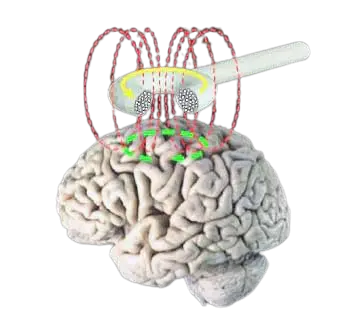

درمان سکته مغزی با rTMS یکی از روشهای نوین و پیشرفتهای است که امروزه بسیاری از متخصصان برای بازسازی مسیرهای عصبی آسیبدیده پیشنهاد میدهند. خوشبختانه شواهد علمی و تحقیقات گسترده نشان میدهند که این تکنولوژی توانسته تأثیرات قابلتوجهی بر بهبود عملکرد حرکتی و شناختی افرادی که دچار سکته مغزی شدهاند، بگذارد. از آنجایی که بازه زمانی طلایی (Golden Time) پس از سکته برای بازتوانی بسیار حیاتی است، انتخاب بهترین دکتر آر تی ام اس در تهران اهمیت دوچندانی پیدا میکند؛ چرا که تنها یک متخصص باسابقه میتواند با تنظیم دقیق فرکانسها، بیشترین تحریک را در نواحی آسیبدیده مغز ایجاد کند.

احتمالاً یکی از سوالهای رایجی که برای اغلب افراد به وجود میآید این باشد که آیا درمان سکته مغزی با آر تی ام اس موثر است یا خیر. در پاسخ به این سوال باید بگوییم یکی از مهمترین روشها و نوین ترین دستگاههایی که برای درمان سکته مغزی به کار گرفته میشود، دستگاه آر تی ام اس بوده که این روش توانسته در چند سال اخیر در حوزههای مختلف درمانی خود را جای دهد. خوشبختانه دستگاه آر تی ام اس اثرات درمانی قابل توجه و بسیار خوبی را بر روی بیماران مبتلا به سکته مغزی بر جای گذاشته است. از این دستگاه امواجی بر روی سلولهای مغزی افراد ساطع میشود که میتواند در نهایت سبب بهبود عملکرد حرکتی و ذهنی افرادی که دچار سکته مغزی شدهاند، شود.

درمان سکته مغزی با دستگاه rtms یکی از کاربردی ترین روش ها برای درمان سکته مغزی می باشد. در این روش درمانی با استفاده از امواج مغناطیسی دستگاه، نواحی مغز که در اثر سکته مغزی آسیب دیدهاند، هدف گذاری شده و این دستگاه کمک میکند تا فعالیت نواحی آسیب دیده مغز بهبود پیدا کند.